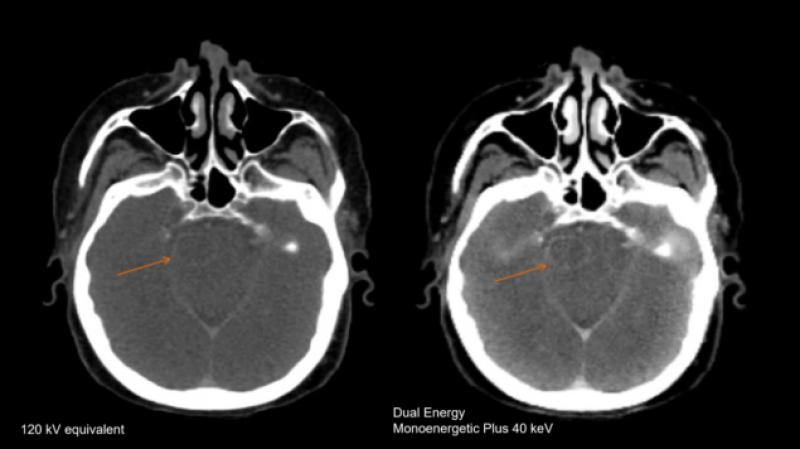

拉合尔 SKMCH&RC 临床和放射肿瘤科主任 Tabinda Sadaf 博士说,该部门拥有五个直线加速器,是该国最大的此类部门,每年提供超过 50,000 次放射治疗。True Beam 直线加速器能够使用精确聚焦的辐射束进行放射治疗,以治疗脑部、颈部、肺、肝、脊柱和其他区域的肿瘤以及其他异常情况。实时肿瘤跟踪可实现高度适形和有针对性放疗精度小于1mm,不影响肿瘤周围正常组织。她还补充说,新的加速器比传统的直线加速器快三倍,每次治疗通常持续不到两分钟。